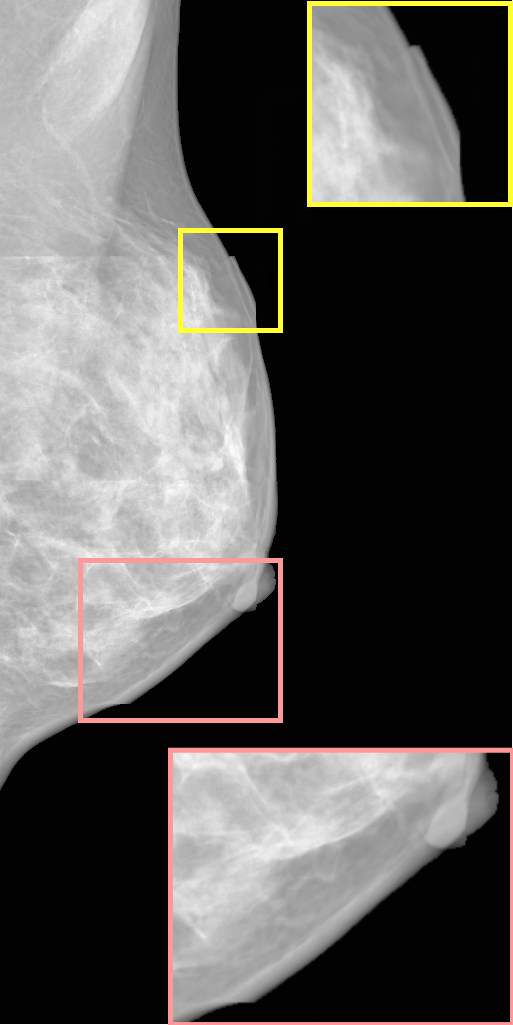

To assess potential memorization, synthetic images produced by MAMBO were compared against real images from the training dataset to identify any significant visual overlap or unintended reproduction. Top-k nearest neighbors were retrieved using cosine similarity in the Mammo-CLIP embedding space [8]. As shown in Fig. 5, even when embedding similarity is high, the generated images differ clearly from the originals in shape, tissue structure, and texture. This indicates that MAMBO’s outputs reflect genuine generalization, not memorization or data leakage.

15 Per-channel Input Examples

Fig. 11 shows samples of per-channel inputs for the mid-resolution and high-resolution models in the MAMBO pipeline.